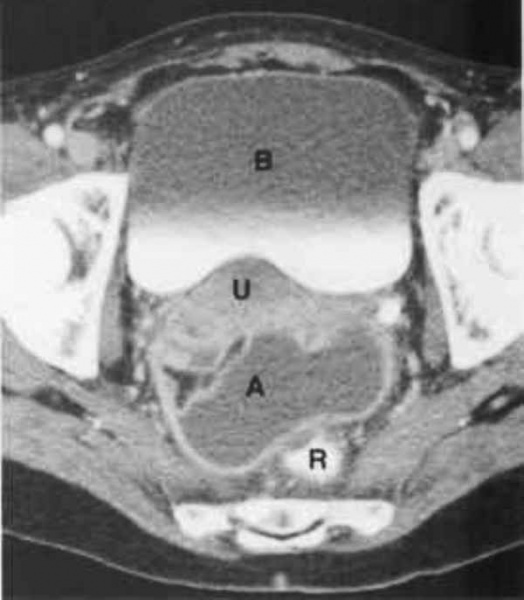

(Слева) При ТВУЗИ у пациентки с двусторонним тубоовариальным абсцессом в левых придатках визуализируется сложное солидно-кистозное образование. Аналогичная картина выявляется в правых придатках. Идентифицировать нормальные яичники не удается.

(Справа) При КТ с контрастным усилением в аксиальной плоскости у той же пациентки выявляются сложные объемные образования в придатках с обеих сторон с толстым ободком усиления и перегородками, накапливающими контрастное вещество, и центральной частью, имеющей низкую рентгеновскую плотность. Тазовая жировая клетчатка имеет тяжистый рисунок, обусловленный воспалительными изменениями, в малом тазу видны свободная жидкость и утолщение брюшины.